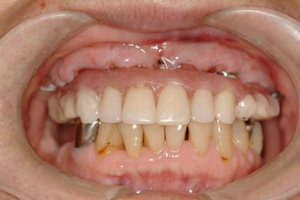

先日行ったall on 4の症例の写真です

前歯しかない患者様で前歯がないと見た目が困るということでお越しになりました

その日入った仮歯です、もちろん固定式で、入れ歯のような取り外しは当日から必要ありません。